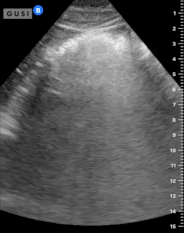

A Point-of-Care Ultrasound exam is performed in the pre-op area which demonstrates:

The cross-sectional area of the gastric antrum appears to be 28 cm². Additionally, there is hyperechoic, shadowing material in the gastric antrum, making it challenging to accurately determine the posterior wall. However, the anesthesiologist interprets this as evidence of solid food in the stomach and utilizes the Perlas formula to estimate approximately 350 mL of food and liquid present.